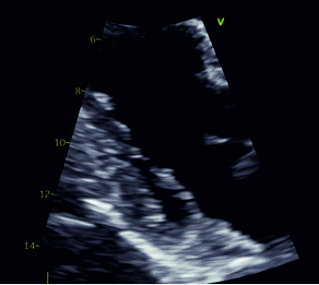

Figure from article: Mitral annular disjunction...

Mitral annular disjunction (MAD) is a structural anomaly of the heart characterized by the displacement of the posterior mitral leaflet’s attachment toward the left atrial wall. MAD can lead to mitral valve prolapse, ventricular arrhythmia, and sudden cardiac death. In the general population, MAD can be found in 7%–9% of individuals. Transthoracic echocardiography is the primary imaging assay for detecting MAD, while cardiac magnetic resonance imaging remains the gold standard. The treatment strategy depends on the severity of mitral regurgitation, the presence of symptoms, and the risk of arrhythmia. Further research is necessary to better characterize this condition and to define optimal diagnostic and therapeutic strategies.